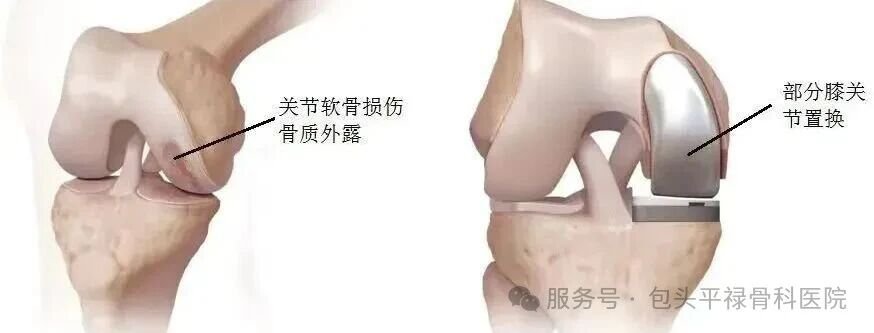

膝关节单髁置换术相当于“局部翻新”,就是只置换“坏掉房间”的磨损表面,仅将受损的软骨和部分骨质去除,替换为人工假体,而完好的软骨、交叉韧带及其他结构都得以最大程度的保留。